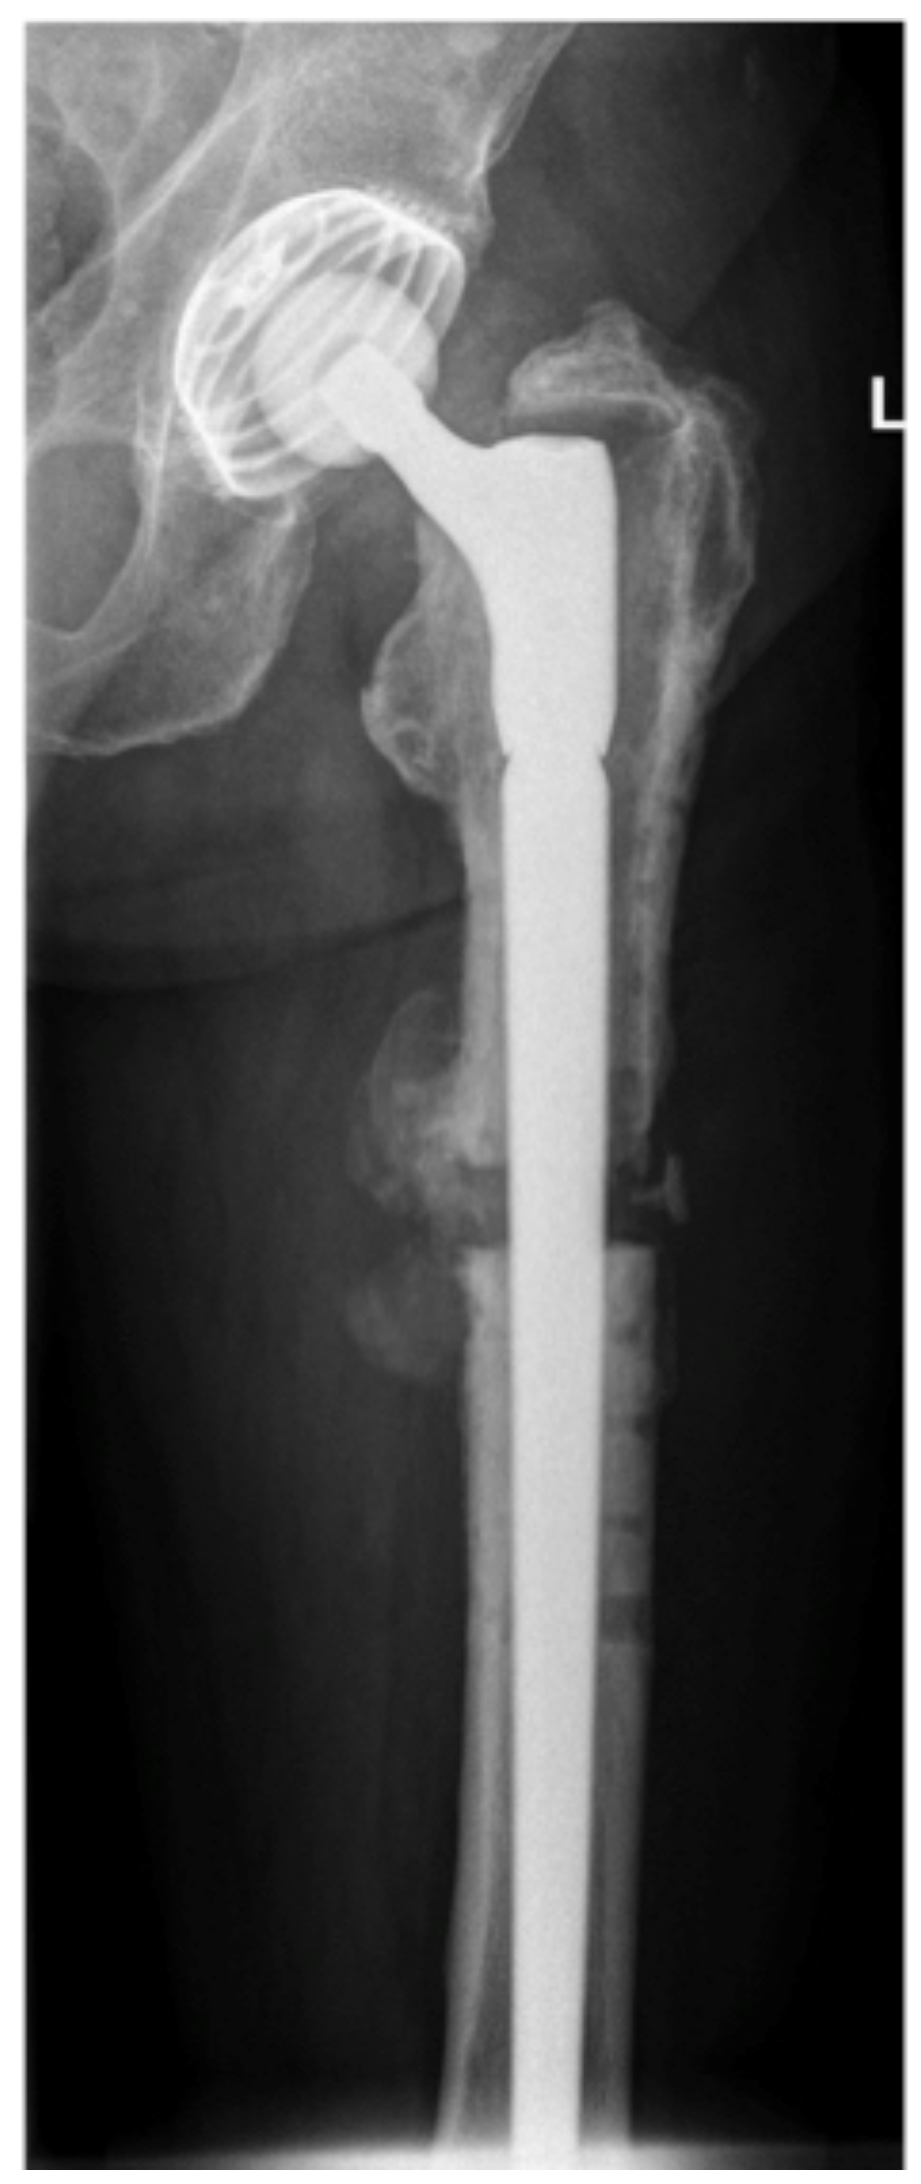

En-Bloc Resection of Metastases of the Proximal Femur and Reconstruction by Modular Arthroplasty is Not Only Justified in Patients with a Curative Treatment Option—An Observational Study of a Consecutive Series of 45 Patients

1. Introduction

2.3. Surgical Technique and Postoperative Care